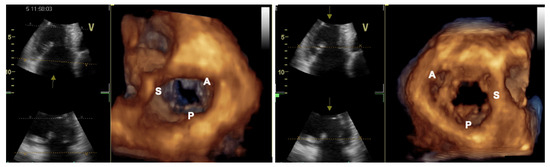

2.1. Two-Dimensional and Three-Dimensional Transthoracic and Transesophageal Echocardiography

3.1. Two-Dimensional and Three-Dimensional Transesophageal Echocardiography